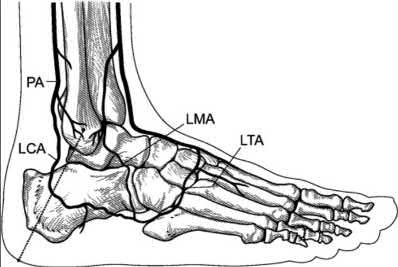

A 70-year-old female with a history of poorly controlled diabetes mellitus presents with purulent ulcers along the plantar aspect of her right forefoot and exposed metatarsal bone. She elects to undergo an amputation. She is insensate to the midfoot bilaterally. Her ankle-brachial index (ABI) for her right posterior tibial artery is 0.4. Further preoperative evaluation demonstrates a transcutaneous oxygen pressure of 45 and an albumin of 3.4. Which of the following would be a contraindication to performing a Syme amputation (ankle disarticulation) in this patient?

A Syme amputation (ankle disarticulation) is a function-preserving amputation option that allows for terminal weight bearing, however strict criteria must be met for a patient to undergo successful Syme amputation. An ankle-brachial index (ABI) less than 0.5 for the posterior tibial artery in a patient with diabetes would be a contraindication for this procedure as success is dependent on the vascular supply of posterior tibial artery to the plantar flap and heel pad.

Pinzur et al retrospectively reviewed their results when performing a single-stage Syme ankle disarticulation in patients with diabetes either for peripheral neuropathy or infection. Patients with ABIs less than 0.5 for the posterior tibial artery had significantly decreased healing rates and smokers had a three-fold increased risk of postoperative infection.